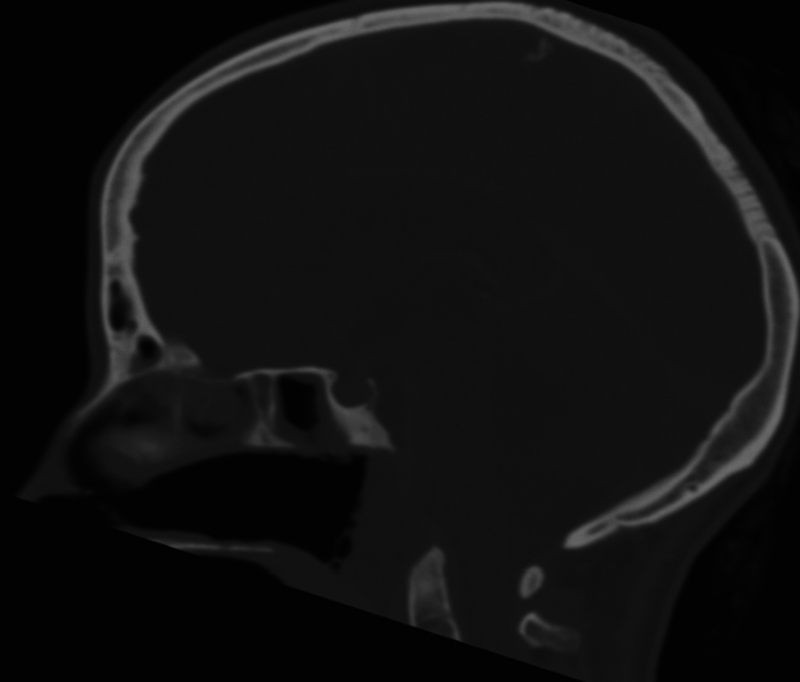

可卡因是苏格兰最常用的消遣性毒品之一,造成重大的社会经济和严重的健康挑战。可卡因引起的中线破坏性病变(CIMDL)的流行率正在上升,由于可卡因的增加。在这里,我们报告一例患者谁发展急性脑积水和脑膜炎作为CIMDL由于长期滥用可卡因的并发症。39岁女性,有慢性鼻用可卡因滥用史,表现为发热、不适和步态不平衡。到达急诊科时,她感觉改变,格拉斯哥昏迷评分(GCS)为10分,左侧偏瘫,需要紧急插管。影像显示急性脑积水及脑水肿。她接受了紧急脑室外引流术(EVD)以缓解颅内压升高。她的一系列问题和生化参数指向急性细菌性脑膜炎的诊断。她的血液培养培养出对甲氧西林敏感的金黄色葡萄球菌,她开始使用广谱抗生素。她的计算机断层扫描显示蝶窦内有空气,斜坡侵蚀,C1前弓部分侵蚀,符合CIMDL。她发展为后循环缺血性中风,这是由于她的心内膜炎和经胸超声心动图检测到的三尖瓣赘生物。最终,她接受了脑室腹腔分流术以永久转移脑脊液。神经学评分为E4V5M6,出院时伴有左侧偏瘫。她正在口腔颌面外科、耳鼻喉科和颅底小组的护理下积极康复。该病例强调了多学科护理和支持在管理此类病例中的重要性,特别是旨在防止感染复发导致显著发病率甚至死亡率。

Cocaine is among the most commonly used recreational drugs in Scotland, contributing to significant socioeconomic and severe health challenges. The prevalence of cocaine-induced midline destructive lesions (CIMDL) is rising due to increased cocaine insufflation. Here, we report a case of a patient who developed acute hydrocephalus and meningitis as complications of CIMDL due to long-term cocaine abuse. A 39-year-old woman with a history of chronic nasal cocaine abuse presented with fever, malaise, and gait imbalance. On arrival at accident and emergency department, she had altered sensorium, Glasgow coma scale (GCS) of 10, and left-sided hemiparesis, requiring emergency intubation. Imaging revealed acute hydrocephalus and brain edema. She underwent an emergency external ventricular drain (EVD) to temporize her raised intracranial pressure. Her constellation of problems and biochemical parameters directed toward a diagnosis of acute bacterial meningitis. Her blood cultures grew methicillin-sensitive Staphylococcus aureus , and she was started on broad-spectrum antibiotics. Her computed tomography scans showed air in the sphenoid sinus, clival erosion, and partial erosion of the anterior arch of C1, consistent with CIMDL. She developed posterior circulation ischemic strokes, which were attributed to her endocarditis and tricuspid valve vegetations that were detected on her transthoracic echocardiogram. Eventually, she underwent a ventriculoperitoneal shunt for permanent cerebrospinal fluid diversion. Neurologically, she was E4V5M6 with residual left hemiparesis at the time of discharge. She is on aggressive rehabilitation under the care of oral maxillofacial surgery, otorhinolaryngology, and a skull base team for her CIMDL. This case highlights the importance of multidisciplinary care and support in managing such cases, especially aiming to prevent the recurrence of infection leading to significant morbidity or even mortality.